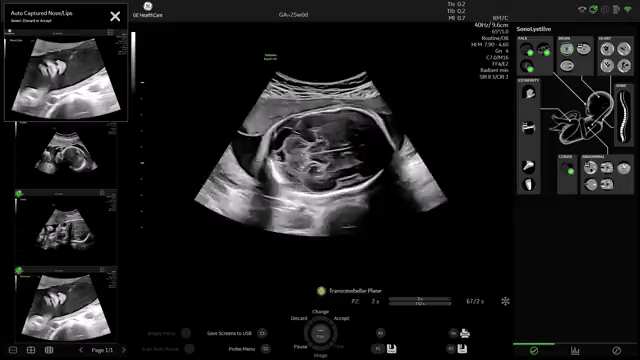

Identifica anatomía automáticamente y ayuda en etiquetado y mediciones.

Reduce interrupciones durante el examen. Menos pausas para documentar.